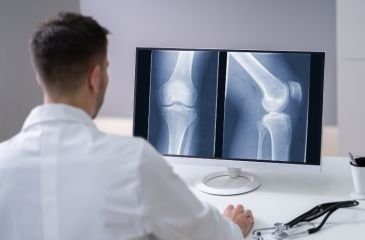

Knee Replacement

Knee replacement surgery is advised when knee arthritis or joint damage causes persistent pain and stiffness that does not improve with medication or therapy. The damaged joint surfaces are replaced with artificial implants to restore alignment, reduce pain, and improve walking ability.

Knee Arthroscopy

Knee arthroscopy is a keyhole procedure used to treat ligament tears, meniscus injuries, cartilage damage, and sports-related knee problems. Small incisions are used to insert a camera and instruments, allowing precise treatment with faster recovery.

Robotic Knee Surgery

Robotic knee surgery uses advanced technology to improve accuracy during knee replacement. It helps in precise implant placement, better alignment, and controlled bone preparation. This approach may improve recovery and long-term joint function.